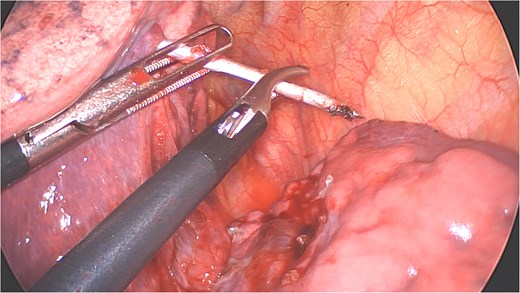

Under general anesthesia with a left double-lumen intubation a left thoracoscopy (VATS) was done using one 11 mm trocar and 2 trocars of 5 mm and a 30° 5 mm camera. We saw a pleural cavity with dense apical adhesions of the left upper lobe against the inferior border of the clavicle (Fig. 3).

Perioperative views of the migrated K-wire, showing dense apical adhesions of the left upper lobe.